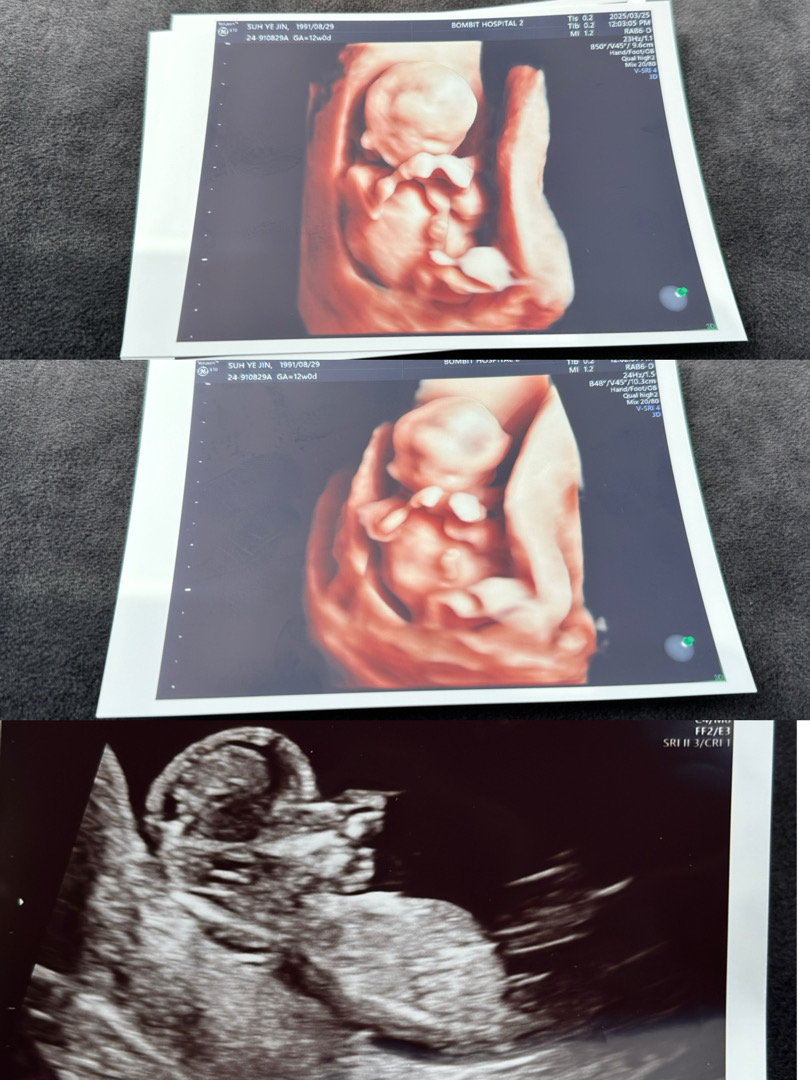

12주차 입체초음파 보고왔는데....!! 성별궁금해요

성별 알 수 있을까요?? 아직 너무 빠르겠죠??🥹

오 아들같아요 정확한건 각도법앱이나 장꾸맘 카페로 가보셔요!